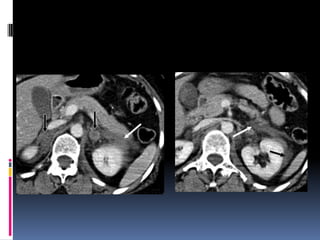

INJURIA HEPÁTICA Grados de severidad RadioGraphics 2009; 29:2033–2053

INJURIA ESPLENICA - Clasificación GRADE DESCRIPTION Hematoma Subcapsular, <10% surface area I Laceration Capsular tear, <1 cm parenchymal depth Hematoma Subcapsular, 10-50% surface area II Intraparenchymal, <5 cm in diameter Laceration Capsular tear, 1-3 cm parenchymal depth which does not involve a trabecular vessel Hematoma Subcapsular, >50% surface area or expanding III Ruptured subcapsular or parenchymal hematoma Intraparenchymal hematoma >5 cm or expanding Laceration >3 cm parenchymal depth or involving trabecular vessels Laceration Laceration involving segemental or hilar vessels IV producing major devascularization (>25% of spleen) Laceration Completely shattered spleen V Vascular Hilar vascular injury which devascularizes spleen

 Segundo órganomas afectado  Lesiones similares a las hepáticas  Sospecha de lesión:  Contornos borrosos  Líquido espacio pararrenal anterior y lateroconal izquierdos  Coágulo centinela

 Pitfalls:  Hendiduras (cleft) congénitos  Artificios de costillas, interfases aire-líquido (estómago, intestino), sondas o catéteres metálicos  Heterogeneidad fase arterial